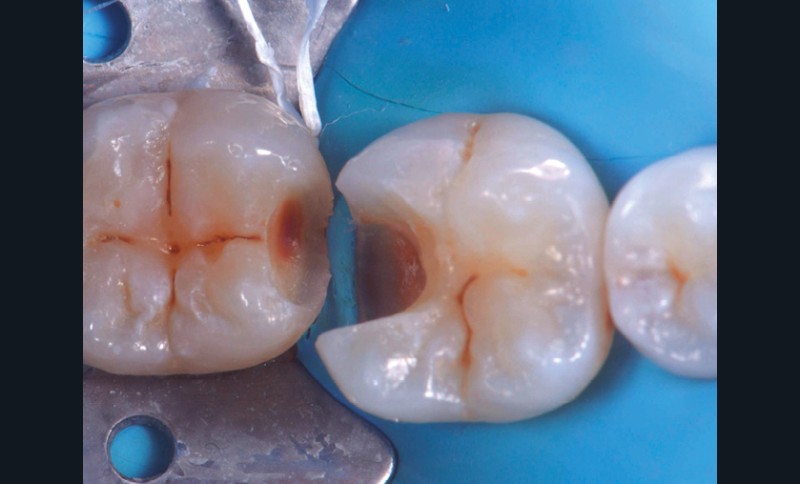

Développé peu avant les années 2000 par Dietschi et Spreafico [7], le concept de Cervical Margin Relocation (CMR) renommé Deep Margin Elevation (DME) en 2012 par Magne et Spreafico [8] consiste à relocaliser coronairement les limites de la préparation en juxta ou supra-gingival. La littérature scientifique nous montre que le parodonte semble tolérer la présence d’une quantité « raisonnable » de composite en sous-gingival.

Cependant, cette technique est opérateur-dépendant et n’est efficace que si l’étanchéité en profondeur a pu être obtenue. À moyen et long terme, si le traitement initial a été correctement mené, c’est le maintien d’une hygiène (inter)dentaire scrupuleuse qui permettra la réussite du traitement [4].

Du point de vue de l’adhésion et des biomatériaux à proprement parler, les intervenants reviendront sur l’importance de la photopolymérisation (types de lampes, importance du temps de polymérisation) et sur le choix du composite de restauration le plus adapté ainsi que sa mise en œuvre pour obtenir un joint résistant (fig. 2 à 6).